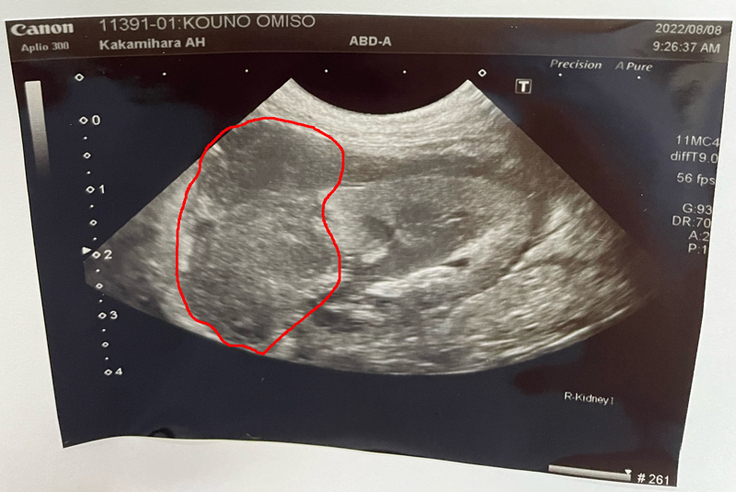

抗がん剤治療17回目

17回目の抗がん剤治療。

前回、白血球の値は基準値内ではありましたが、今までの治療での最低値を若干上回るものの、一番強い薬での治療では心配もあり、おみそへの負担が軽い、初期の抗がん剤治療薬での施術となりました。

本来であれば、数週間前の治療で、腫瘍が小さくなり始めた状態での追い打ちをかける強めの抗がん剤治療が出来れば良かったのですが、おみその生命に関わる為、治療を延期しました。ある程度予想はしていたものの、やはり今回、腫瘍が大きくなっていました。

抗がん剤治療をしているとは言え、他の事例をみても生命維持している事で、おみそ自身、頑張っているとの見解でした。確かに普段の生活では普通に過ごしているように感じます。抗がん剤の副作用である、髭の抜け落ちも無く、不思議なくらいです。

以後、おみその体の具合をみながら、抗がん剤治療が続きます。